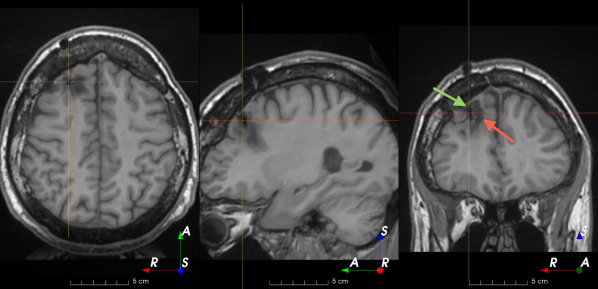

Refer to caption

(a)

(b)

(c)

(d)

(e)

(f)

(g)

(h)

Figure 6: Examples of challenging images for cavity segmentation. (a) Small frontal lesionectomy surrounded by hypointense white matter (b) Brain shift after contralateral temporal lobectomy (not shown) (c) Small frontal lesionectomy near the Sylvian fissure (d) Lack of boundaries between oedema and resection cavity (e) Possible blood clot within the cavity (f) Brain shift, oedema and resection cavity (g) Arachnoid cyst and resection cavity (h) Cerebellar degeneration. Green annotations represent areas that correspond to resection cavities; red annotations represent areas that do not.